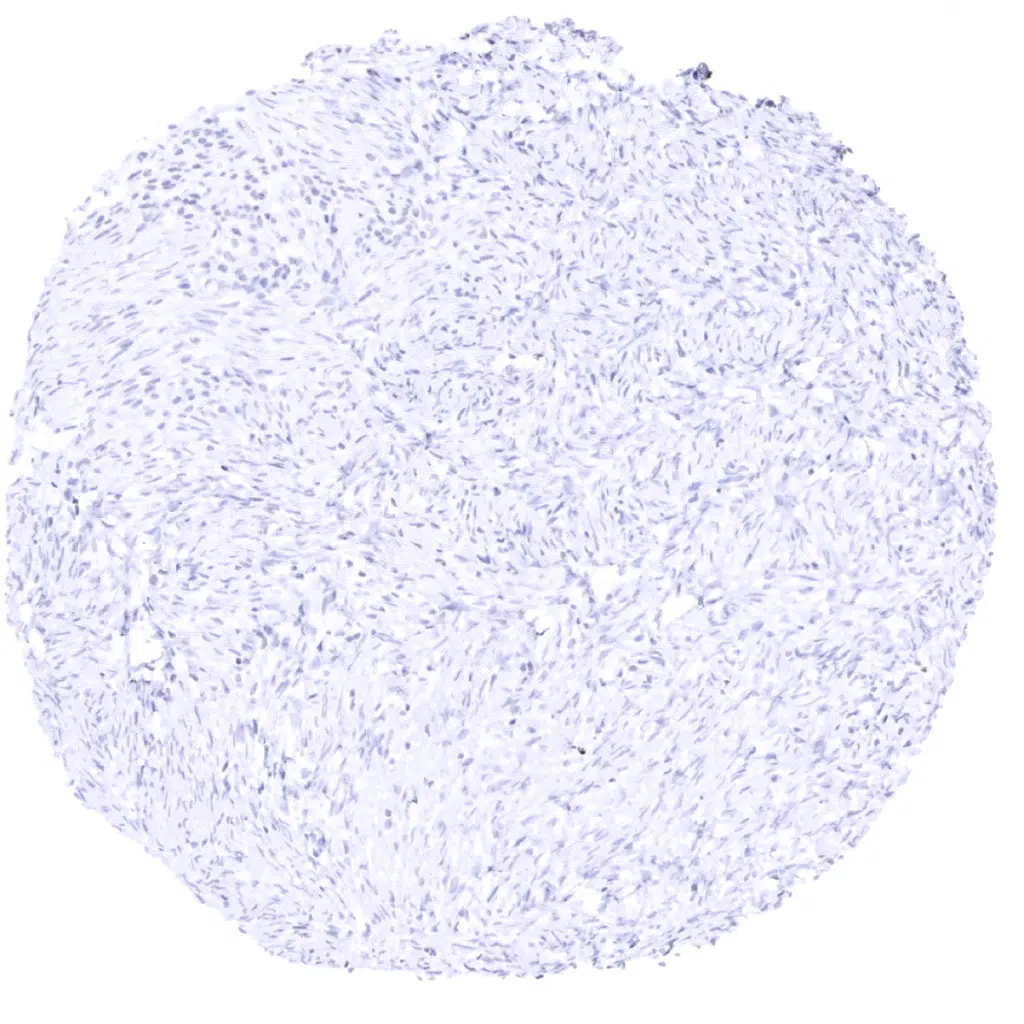

Uterus, myometrium